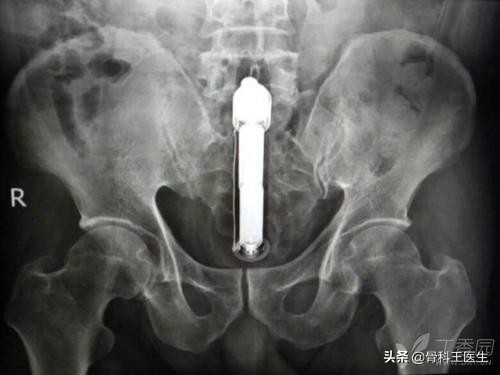

4、肛门、结直肠取异物:

说到从肛门进去,那我们取的东西就太多了,这地方太能装了。

下图你们知道是什么吗?王医生羞羞的表示并不认识:

不认识就不发了,我们发一些认识的: